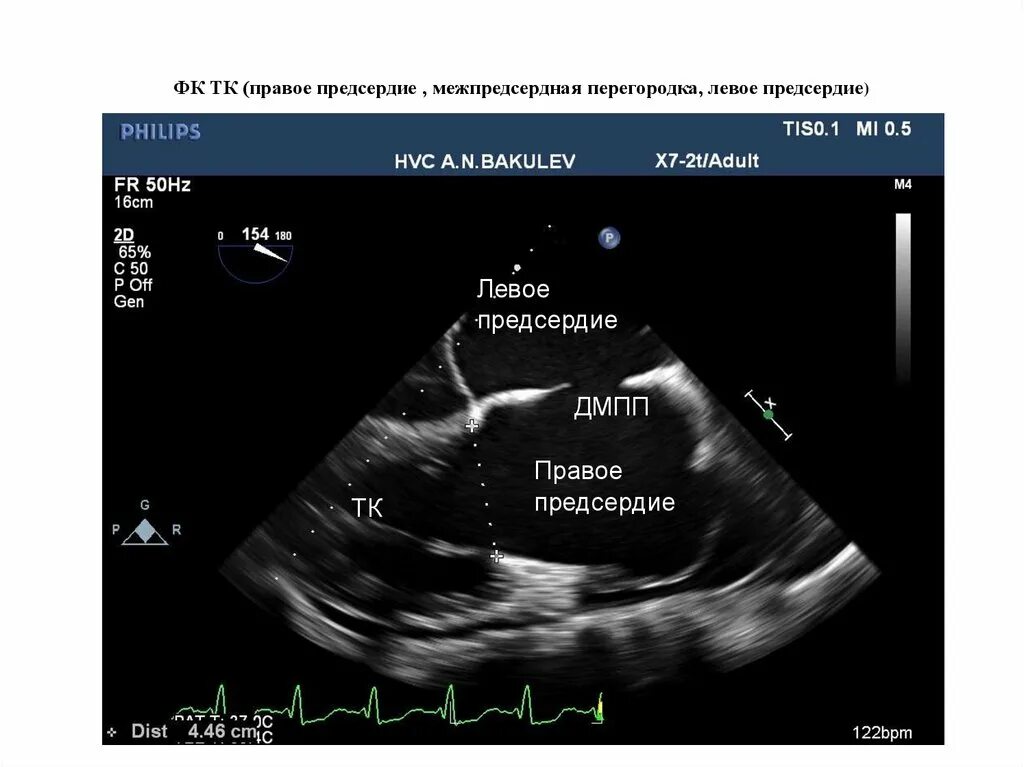

Перегородка в левом предсердии